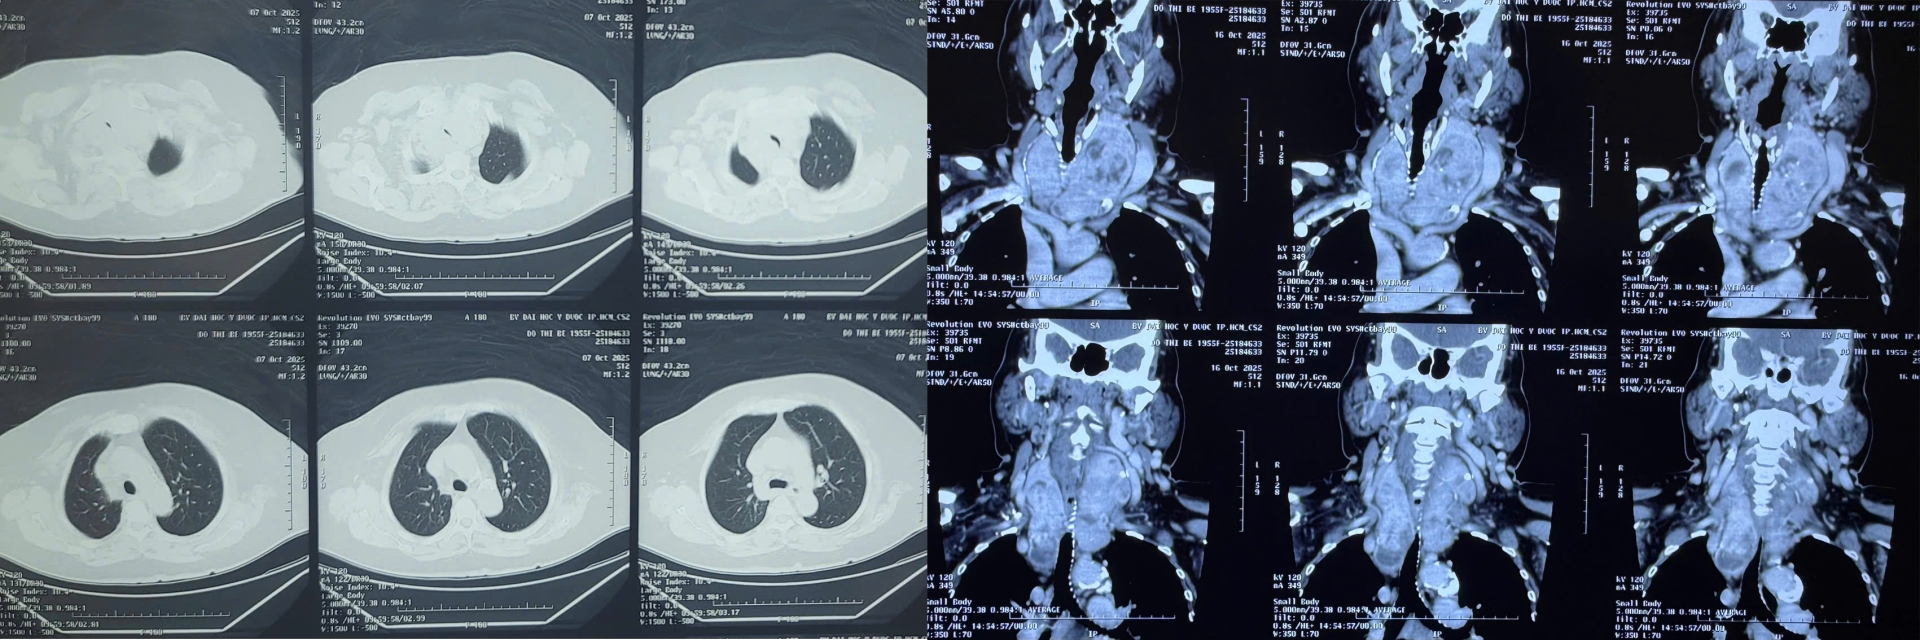

Kết quả kiểm tra cho thấy bà bị bướu giáp thòng trung thất kích thước lớn, chèn ép gần như toàn bộ khí quản, khiến việc hô hấp vô cùng khó khăn.

“Đây là một ca mổ không hề đơn giản. Bướu giáp thòng xuống sâu, ôm sát khí quản và các mạch máu lớn trong trung thất. Chỉ cần sơ sẩy, bệnh nhân có thể mất đường thở ngay trên bàn mổ. Nhưng may mắn là ca phẫu thuật diễn ra thuận lợi, chúng tôi đã lấy trọn khối bướu, giải phóng hoàn toàn đường thở cho bệnh nhân.”

“Đường thở của bệnh nhân bị chèn ép nghiêm trọng, gần như xẹp hẳn ở đoạn dưới thanh quản. Việc gây mê và đặt nội khí quản vô cùng khó khăn, đòi hỏi sự phối hợp nhịp nhàng giữa các bác sĩ phẫu thuật và gây mê để đảm bảo an toàn tuyệt đối. Chúng tôi phải vừa kiểm soát đường thở, vừa theo dõi sát huyết áp, nhịp tim, oxy máu từng giây.